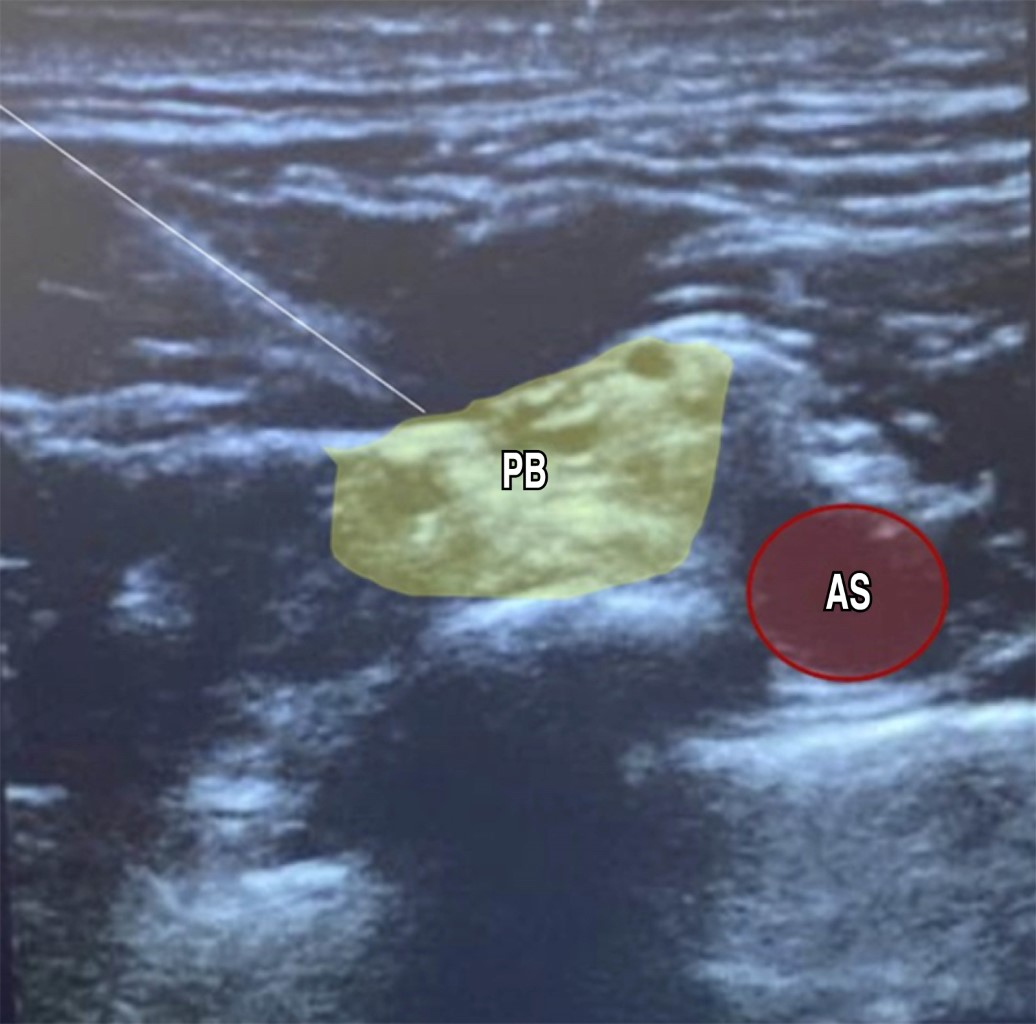

Ultrasound-guided bilateral brachial plexus block, supraclavicular and infraclavicular approach in upper limb surgery plus ultrasound-guided monitoring of diaphragmatic dynamics. A case report

Introduction: in anesthetic practice, bilateral brachial plexus block (BPB) is generally contraindicated due to the risks it entails, systemic toxicity from local anesthetics and bilateral phrenic nerve palsy. Since its indications are scarce, we present the case of a patient who was managed with bilateral regional anesthesia for both upper limbs at the same surgical time. Case presentation: 60-year-old male patient with diagnoses of Frikman III right distal radius fracture and Mayo III left olecranon fracture, scheduled for open reduction and internal fixation (ORIF) of the left olecranon and of the right distal radius, history of type 2 diabetes, systemic arterial hypertension and compensated chronic heart failure. Interventions: left supraclavicular and right infraclavicular BPB were performed as the only anesthetic procedure for bilateral upper limb surgery. Results: bilateral BPB was successful for bilateral upper limb surgery. The surgery was uneventful and without major complications. Conclusions: bilateral brachial plexus block is a safe technique when performed in different approaches, trying to minimize the risk of complications, providing better comfort in the immediate postoperative period of the patient by providing prolonged analgesia.

Figure 3